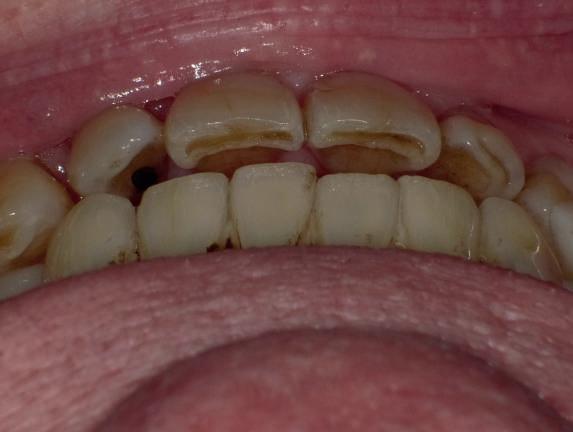

Examinarea parodontală a relevat sângerări generalizate la sondare și adâncimi de sondare de până la 9 mm la molarii maxilari și mandibulari, cu multiple furcații implicate la fiecare molar (fig. 2-7). Prezenta mobilitate multiplă de clasa I la dinții posteriori și de clasa II la dinții nr. 16 și 21 (molarul prim maxilar drept și incisivul central maxilar stâng).

2-4. Imagini înainte de tratament: lateral dreapta (fig. 2), frontal (fig. 3) și lateral stânga (fig. 4). Notă: Molarul prim maxilar drept (dintele 16) (fig. 2) ar fi identificat ca fiind molarul cel mai afectat parodontal care era planificat să fie menținut.